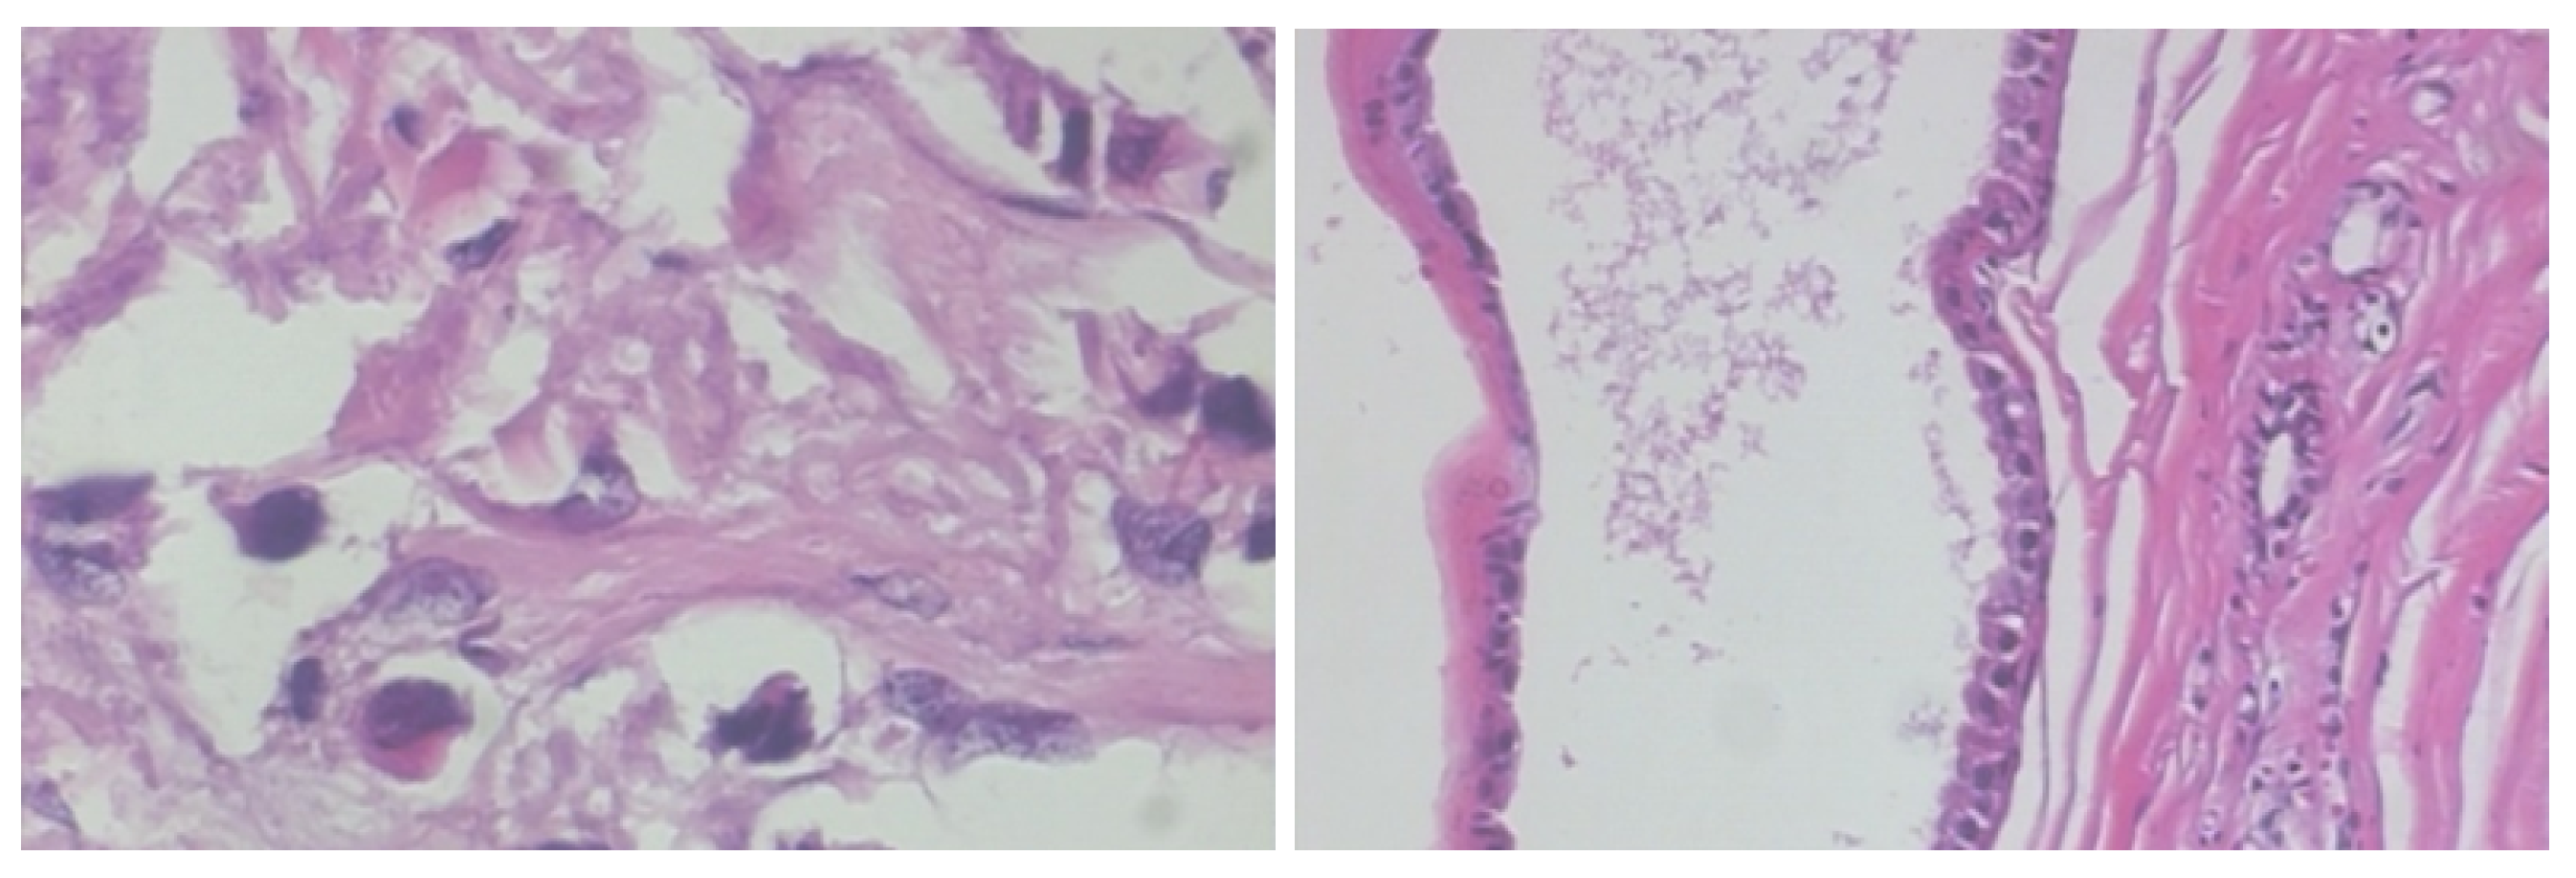

2.1. BreakHis Breast Cancer Histopathological Image Dataset